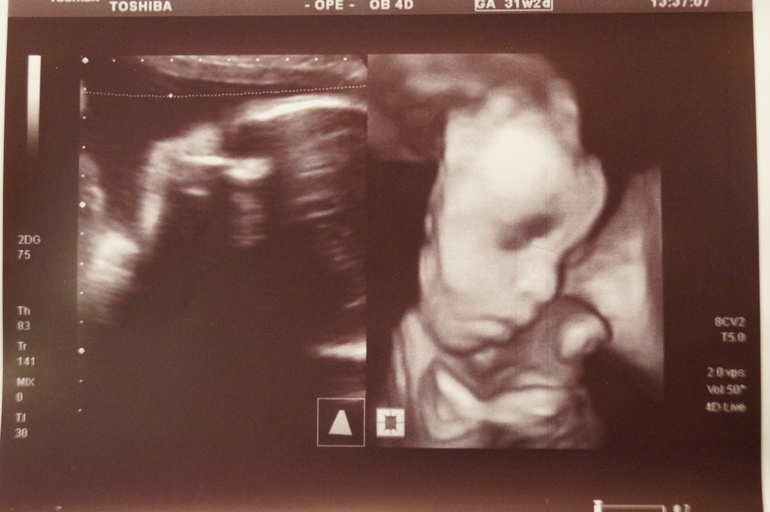

Ну, и по традиции фотки нашей зайки...

Опять-таки фото девчачьего "пирожка". Уж четвёртое-то узи не должно ошибиться!!!!